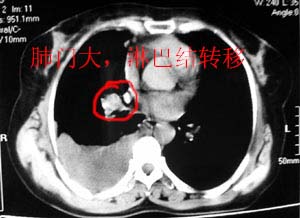

图像不是太好,但可以见到下列恶性征象:

1 单侧肺门增大

2 纵隔侧胸膜明显增厚

3 肋胸膜结节影

结合纵隔略宽、单侧胸水首先考虑肺癌。

以下是引用gaozhengyi在2006-4-12 7:18:00的发言:[br]图像不是太好,但可以见到下列恶性征象:[br]1 单侧肺门增大[br]2 纵隔侧胸膜明显增厚[br]3 肋胸膜结节影[br]结合纵隔略宽、单侧胸水首先考虑肺癌。

在加右腋下淋巴结肿大

右侧胸膜结节状增厚伴胸腔积液及纵隔、腋窝淋巴结肿大,考虑胸膜间皮瘤可能性大;建议胸膜活检。

右侧中央型肺癌合并阻塞性肺炎及右侧胸膜转移。

右侧肺门淋巴结肿大,伴大量胸腔积液,同侧胸膜结节样增厚,有胸膜粘连,考虑肺癌.